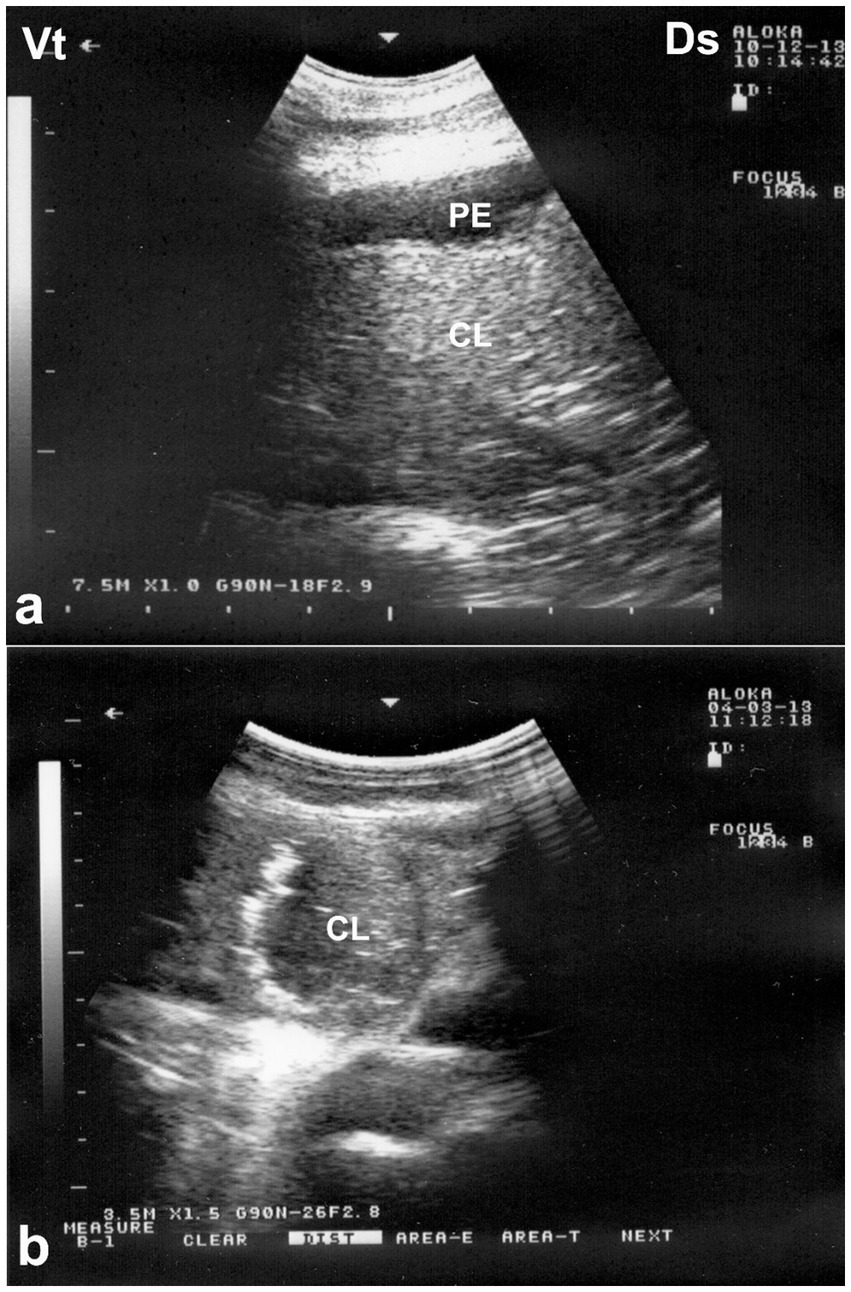

Ultrasonography is considered the most reliable and practical tool for diagnosing pleural effusion in camels, particularly in the absence of accessible radiographic facilities. Sonographic findings typically include an anechoic or hypoechoic fluid accumulation between the visceral and parietal pleura, with displacement or compression of adjacent lung tissue. Fibrin strands, septations, and floating echogenic debris may also be visualized, particularly in exudative or chronic effusions (8). Ultrasonography not only enables accurate assessment of the volume and nature of pleural fluid but also guides safe and effective thoracocentesis, fluid sampling, or drainage procedures. Furthermore, it facilitates serial monitoring of disease progression and response to therapy, thereby enhancing clinical decision-making and prognosis (32). In dromedaries presenting with clinical signs of pleural effusion, ultrasonographic examination reveals hypoechoic to anechoic fluid within the pleural cavity, located between the parietal pleura, diaphragm, and lung. Echogenic strands or fibrin may be visible within this fluid. The accumulation of pleural fluid causes compression atelectasis, particularly in the cranial lung lobes, which appear hypoechoic. Entrapped air in larger bronchi appears hyperechoic and is often accompanied by comet-tail artifacts. Fibrin is visualized as thin, filamentous strands floating within the effusion, loosely attached to the pleural surfaces. It is also common to observe fluid pockets separated by fibrin strands (32) (Figure 12).

Figure 12. Ultrasonographic evidence of pleural effusion in a dromedary camel calf. (a) Longitudinal ultrasonographic image of the right hemithorax showing an anechoic pleural space between the collapsed lung surface and the thoracic wall, consistent with a free, transudative pleural effusion (PE). The underlying lung is partially visualized as a compressed, hypoechoic structure. (b) Left thoracic ultrasound image demonstrating fibrinous pleural effusion (FPE), characterized by multiple echogenic fibrin strands floating within the anechoic fluid. These suspended echogenic bands are indicative of an exudative or inflammatory process, typically associated with infectious pleuropneumonia. Ds – Dorsal; Vt – Ventral [modified from Tharwat (32)].